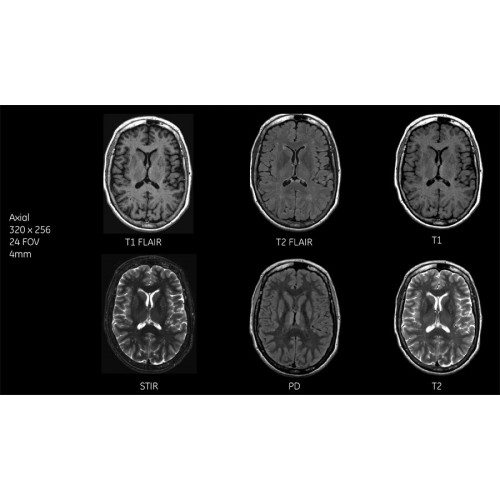

Магнитно-резонансный томограф GE SIGNA Voyager 1.5T представляет собой передовое диагностическое решение, сочетающее в себе высочайшее качество визуализации, комфорт для пациентов и удобство работы для медицинского персонала. Это оборудование открывает новые возможности для точной диагностики широкого спектра заболеваний.

МРТ аппарат GE SIGNA Voyager 1.5T позволяет проводить полный спектр магнитно-резонансных исследований, включая нейровизуализацию, исследования опорно-двигательного аппарата, органов брюшной полости и малого таза, а также специализированные кардиологические программы.